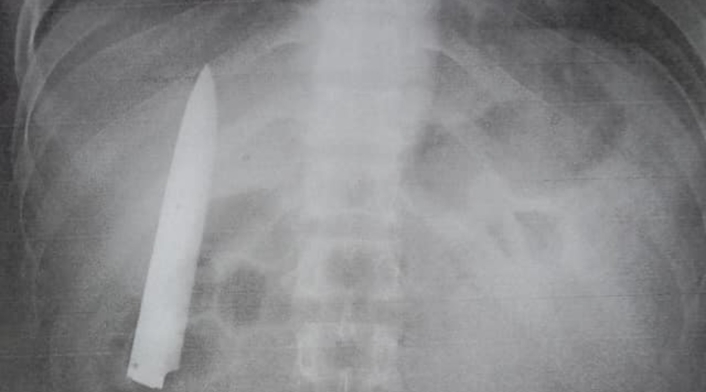

Un hombre sobrevivió catorce meses con una hoja de cuchillo dentro de su torso. El insólito caso se presentó en la ciudad de Kidapawan, Filipinas.

Kent Ryan Tomao fue víctima en enero de 2020 de una brutal agresión por parte de unos adolescentes que lo apuñalaron. El personal médico que lo atendió en aquella ocasión, en una evidente irresponsabilidad, no le realizó exámenes para verificar la profundidad de la herida, sino que procedió a suturarla.

Hace unos días, Tomao aplicó a un empleo en ese país, por lo que le solicitaron unos requisitos en los que incluía una prueba de rayos X. De esta forma, el hombre se dio cuenta que llevaba catorce meses con la hoja de un cuchillo en el interior de su cuerpo.

Al ser preguntado por medios locales, como ABS-CBN, si nunca notó la presencia de un objeto extraño en su torso, Tomao aseguró que cuando el clima era frio sentía algo de dolor en el pecho, pero no le prestaba atención.

Asimismo, explicó que el cuchillo debe ser extraído lo más pronto posible, ya que se encuentra muy cerca de los pulmones y corre riesgo su vida.